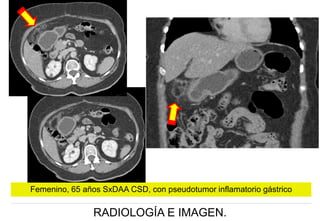

Femenino, 65 años SxDAA CSD, con pseudotumor inflamatorio gástrico

RADIOLOGÍA E IMAGEN.